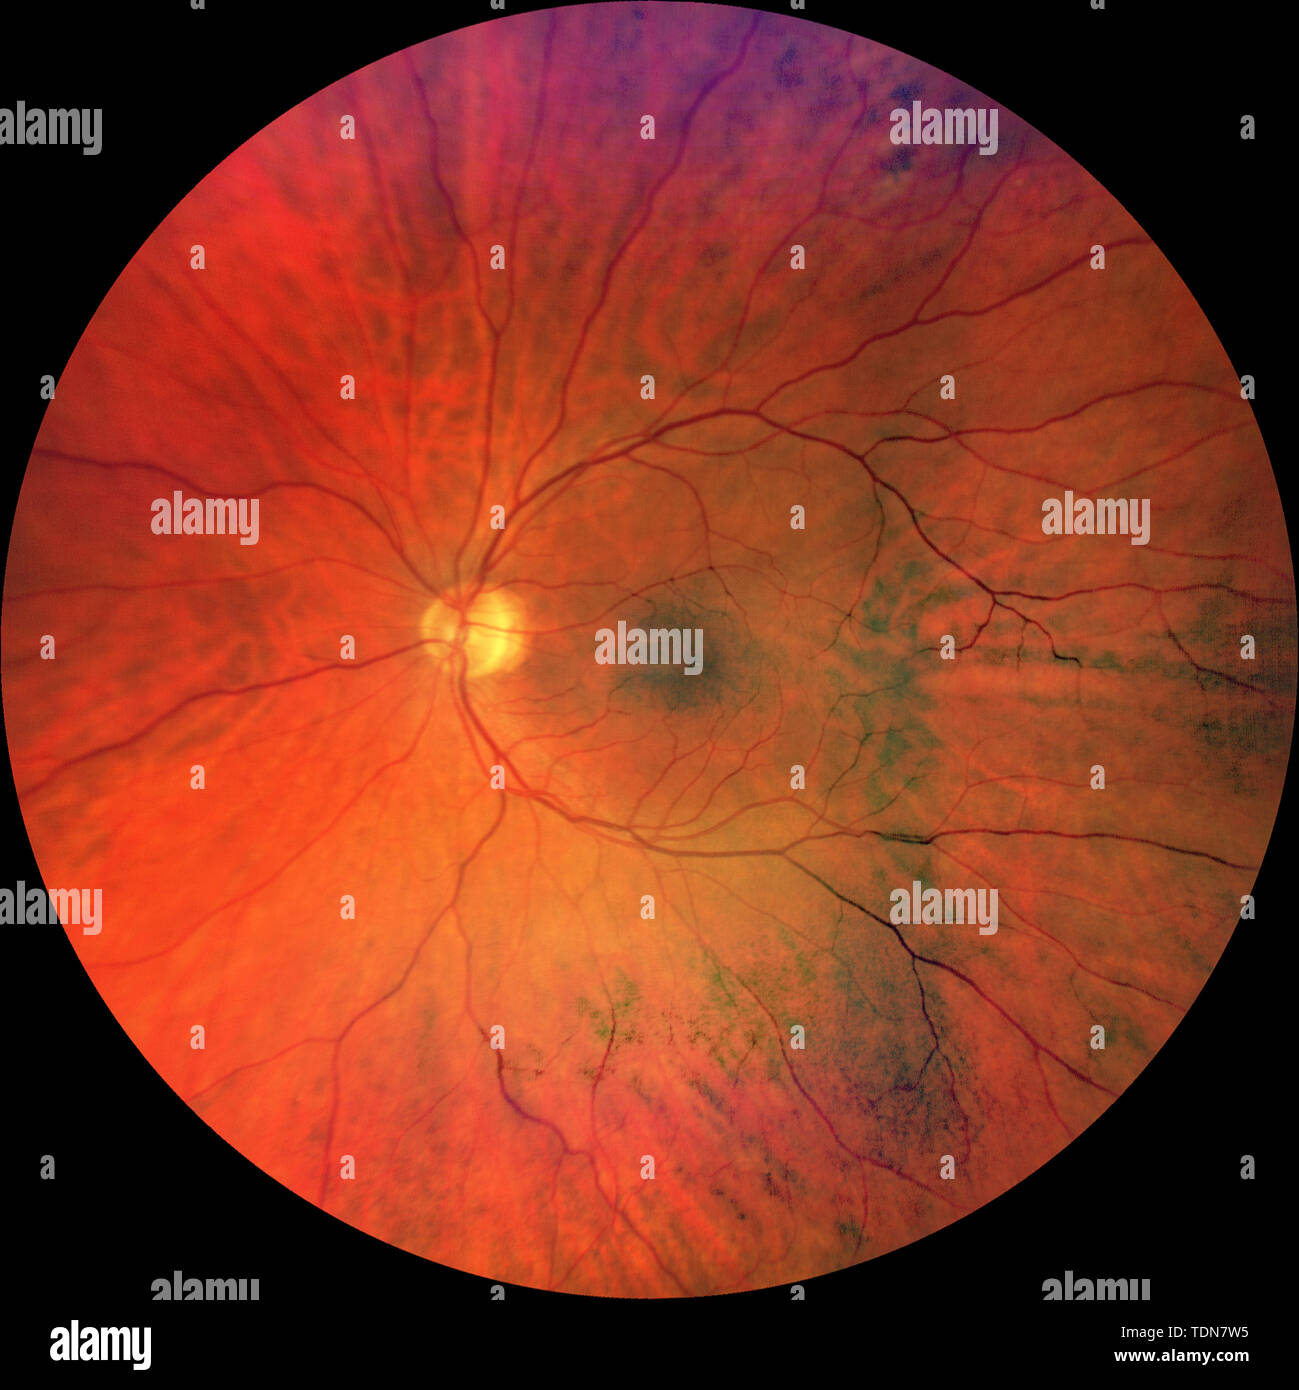

Photograph of the Fundus Oculi: left and right eye Stock Photohttps://www.alamy.com/image-license-details/?v=1https://www.alamy.com/photograph-of-the-fundus-oculi-left-and-right-eye-image249402864.html

Photograph of the Fundus Oculi: left and right eye Stock Photohttps://www.alamy.com/image-license-details/?v=1https://www.alamy.com/photograph-of-the-fundus-oculi-left-and-right-eye-image249402864.htmlRMTDN7W4–Photograph of the Fundus Oculi: left and right eye

Photograph of the Fundus Oculi: left eye Stock Photohttps://www.alamy.com/image-license-details/?v=1https://www.alamy.com/photograph-of-the-fundus-oculi-left-eye-image249402865.html

Photograph of the Fundus Oculi: left eye Stock Photohttps://www.alamy.com/image-license-details/?v=1https://www.alamy.com/photograph-of-the-fundus-oculi-left-eye-image249402865.htmlRMTDN7W5–Photograph of the Fundus Oculi: left eye

Photograph of the Fundus Oculi: right eye Stock Photohttps://www.alamy.com/image-license-details/?v=1https://www.alamy.com/photograph-of-the-fundus-oculi-right-eye-image249402887.html

Photograph of the Fundus Oculi: right eye Stock Photohttps://www.alamy.com/image-license-details/?v=1https://www.alamy.com/photograph-of-the-fundus-oculi-right-eye-image249402887.htmlRMTDN7WY–Photograph of the Fundus Oculi: right eye